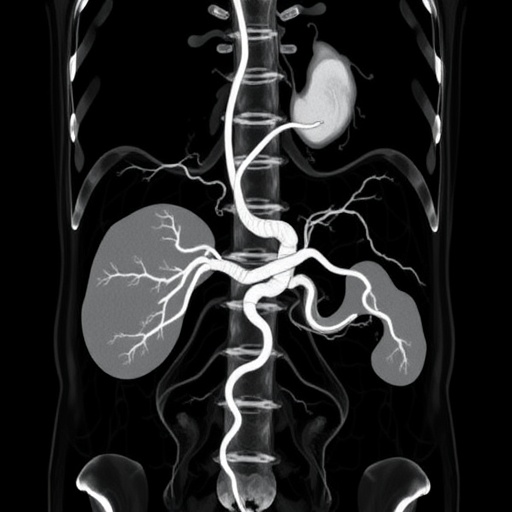

Abdominal aortic aneurysms are characterized by an abnormal dilation of the aorta in the abdominal region, which can lead to life-threatening ruptures if not identified and monitored effectively. Traditional methods of predicting aneurysm outcomes have primarily relied on generalized models that do not take into account the biological differences between sexes. However, this new study highlights the shortcomings of such one-size-fits-all methodologies, advocating for a more nuanced approach that accounts for sex differences in the pathophysiology of AAAs.

In the pursuit of developing effective classification models, researchers employed advanced machine learning techniques to analyze vast datasets derived from AAA clinical records. By examining variables such as genetic predispositions, lifestyle risk factors, and physiological differences, the researchers were able to create models that exhibited improved predictive capabilities. These models have shown that men and women may respond differently to the same pathological processes, thus necessitating tailor-fit algorithms for better outcome predictions.